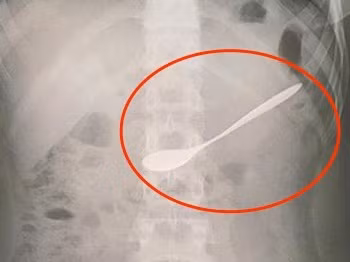

| Ảnh chụp X-quang chiếc thìa trong dạ dày bệnh nhân. |

Các bác sĩ đã nội soi, gắp ra chiếc thìa dài 7 cm từ dạ dày bệnh nhân. "Rất may chiếc thìa không có cạnh sắc nhọn nên không làm tổn thương dạ dày bệnh nhân", bác sĩ cho hay.